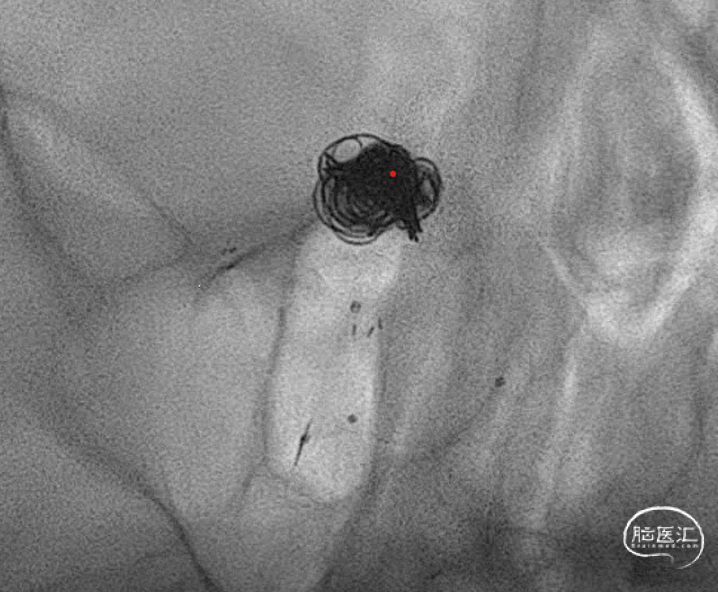

连续填了两枚圈,微导管头没变,但是开始左右摆圈。不好,根据以往经验,瘤顶偏右侧的空间要丢掉机会,如果再填一个圈,即将把动脉瘤颈部偏右侧大脑后动脉部分填致密,这样的话残留在瘤顶部的空白处可能填不上,因此直接采取下一方案。于是趁着瘤颈还有空间,将右侧支架导管撤下,将头塑型为指头或单弯,穿支架网孔到位。

这是微导管到位就放心了,但是一定注意,穿网孔微导管可能有阶梯效应,使其弹射,因此一定要控制好张力,减少戳破动脉瘤的风险。

管他如何,先填个圈把这一部分添上。接下来就是考虑把动脉瘤偏左侧进行正常填塞。